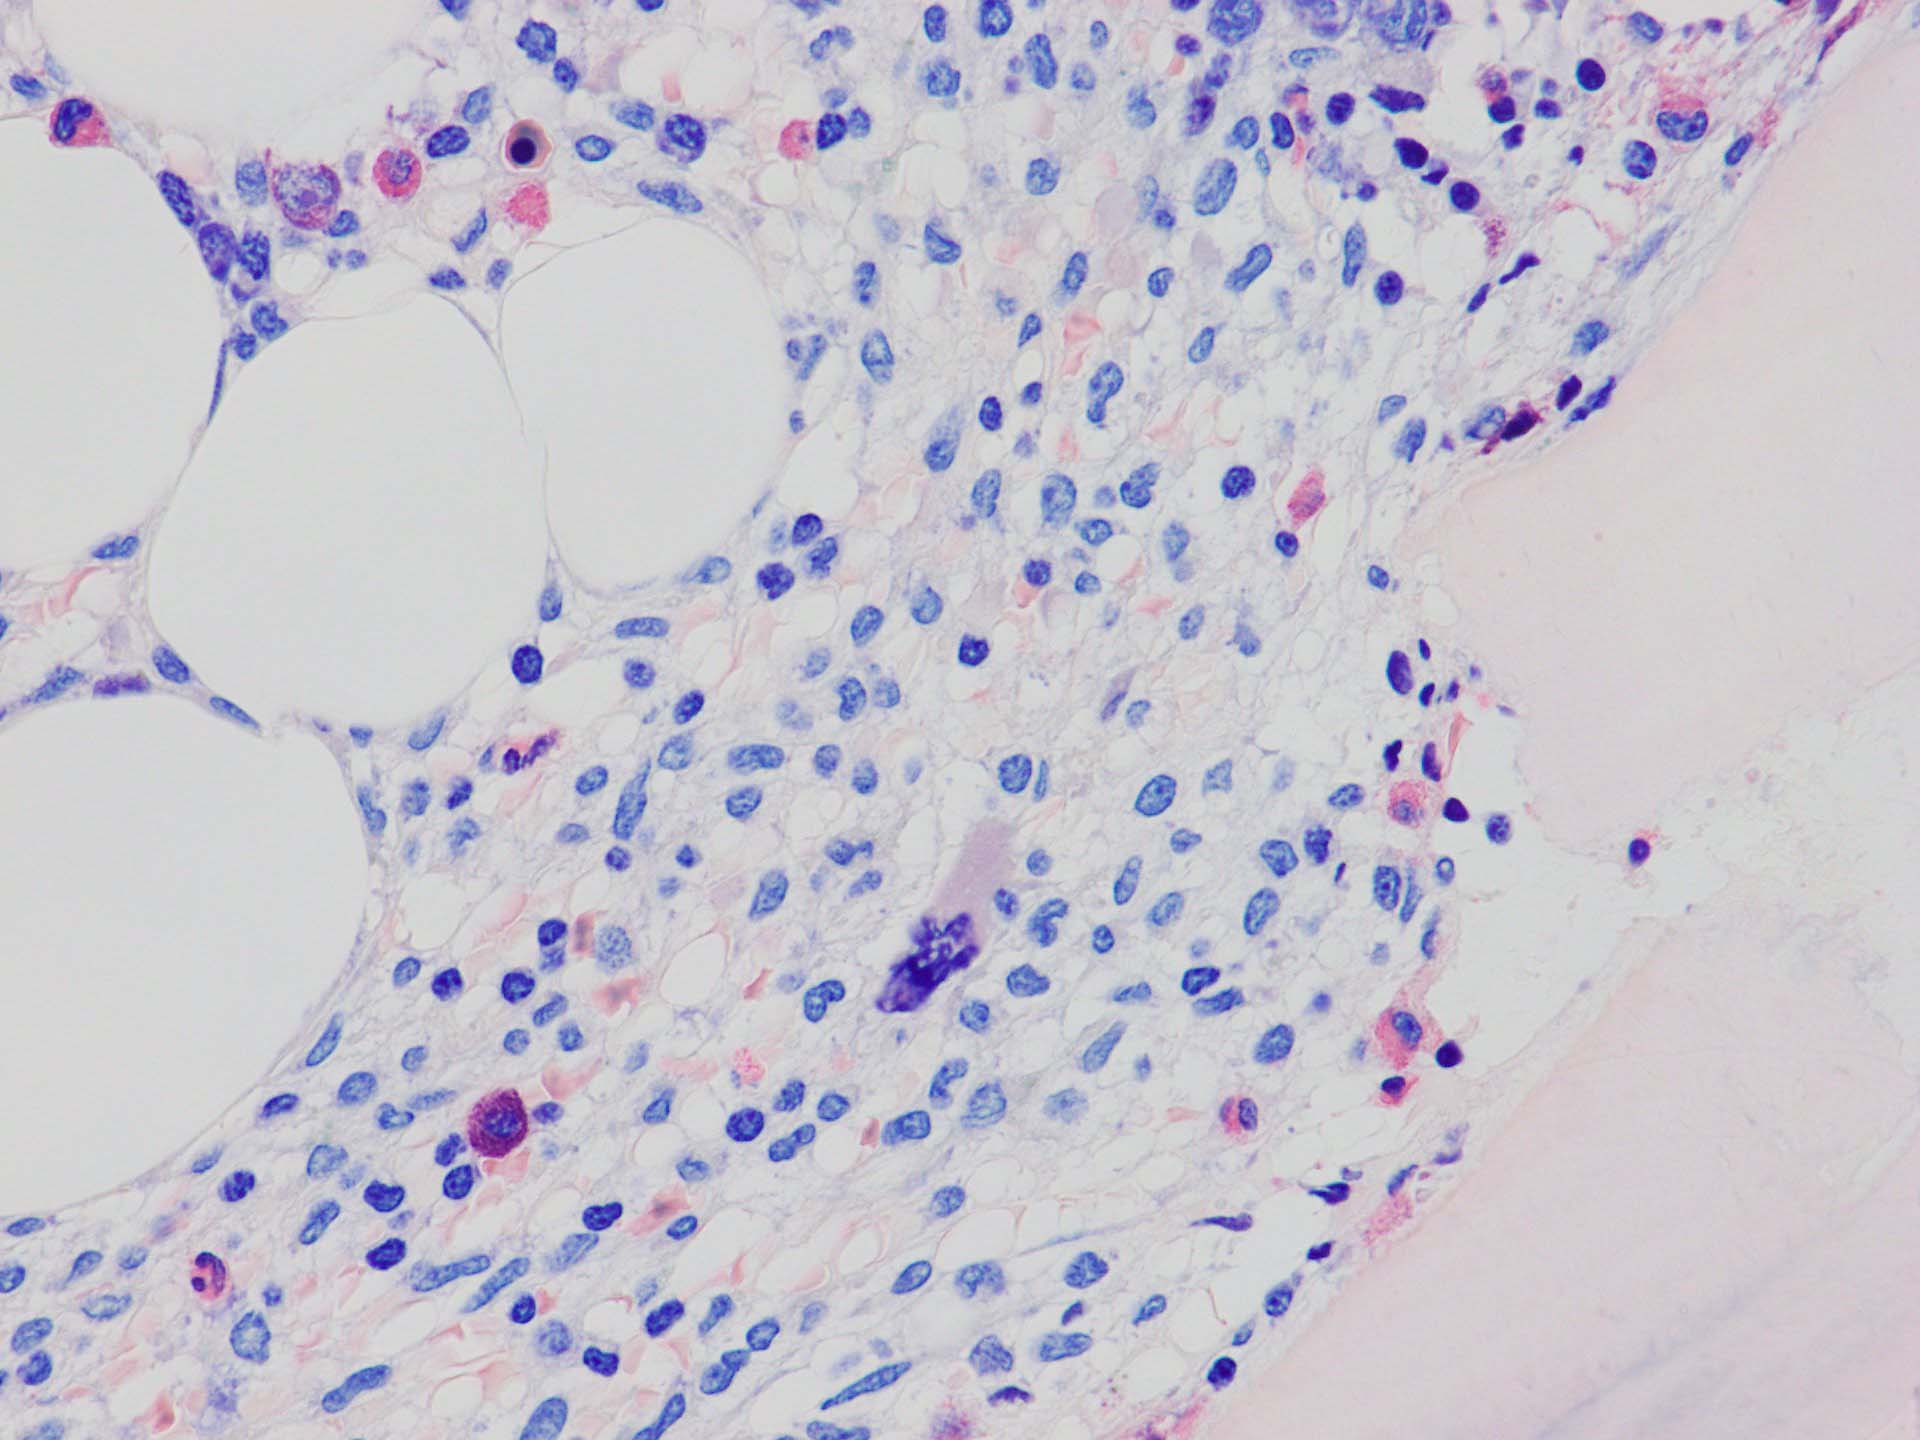

ASD-G 低倍率所見では赤芽球血島は幼若赤芽球の集簇巣が散在する, 顆粒球系細胞(ASDに赤く染色される)は減少,granulopoietic hypoplasiaを呈する.疎な集簇を示すmast cellsの増加がある.

ASD-G陰性の細胞がびまん性に増加しているように見える.

ASD-Giemsa陰性の細胞がシート状に増殖する. 核はクロマチン濃染, 核小体は不明瞭.類円形, 卵円形, くびれを持つ多稜形核, 長円形いびつで屈曲した核, など多彩. 細胞質は淡清色調, 広く淡明. 赤芽球血島は幼若赤芽球のみで形成される異形成像を示す. やや離れて成熟赤芽球が疎な集簇を示す.